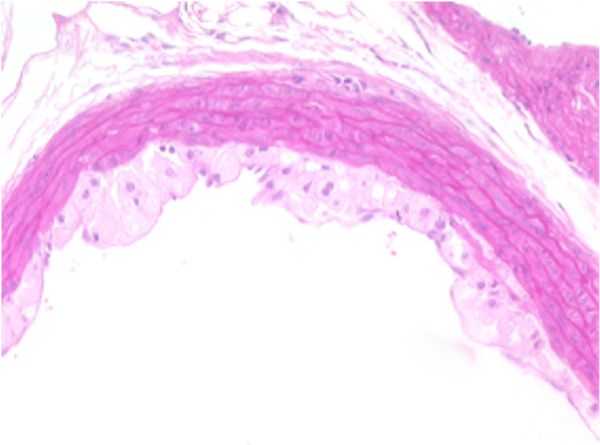

AORTA-a

AORTA–a: Stain: Elastic Fiber. F19-01

Early Atherosclerotic plaque formation, tunica intima, thoracic aorta.

Representation of an accumulation of lipoid filled or foam cells of the xanthomatous type occupying and expanding the subendothelial space, effectively separating the endothelial cell layer from the internal elastic membrane of the tunica intima. The wall of the aorta is mildly thickened by this accumulation of material and the internal elastic membrane appears to be intact within this segment.

This response represents early atherosclerotic plaque formation localized within the tunica intima. The rest of the artery appears to be within normal limits.